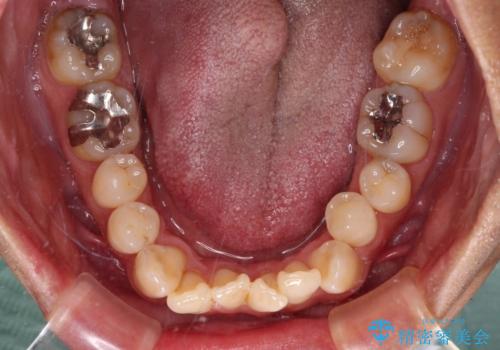

- 前歯のデコボコとクロスバイトを気にして来院された患者様です。

40代半ばであり、あまり周りに気を遣われずに治療を進めたいとのことで、インビザラインにて矯正治療を行うこととしました。

毎日22時間の装着時間をきっちりと守ってくださり、1年半かけずに思い通りの歯列に仕上げることができました。